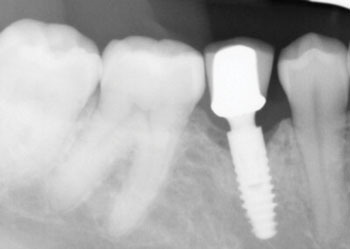

The following radiographs demonstrate representative surgical cases treated with a laser-assisted protocol, illustrating resolution of peri-implant radiolucency, stabilization of crestal bone levels and improved bone density patterns over time.

Fig. 2 depicts a dental implant at site #31 that presented with peri-implant probing depths of 12 mm on both the mesial and distal aspects, accompanied by suppuration. A 12-month follow-up radiograph reveals substantial peri-implant bone fill on both the mesial and distal aspects.

Fig. 2: Initial and follow-up radiographs of dental implant at site #31.